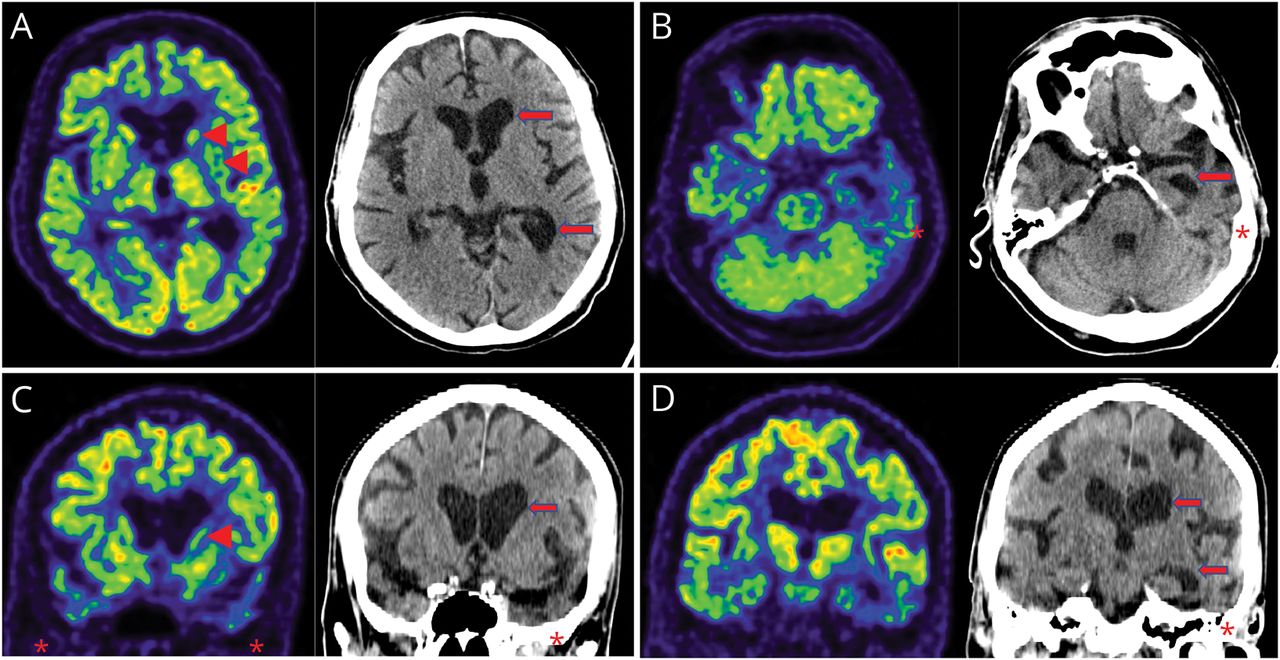

神经FDG PET / CT显示不对称(左比右)颞叶萎缩与葡萄糖代谢减退。有降低新陈代谢的头部的左侧尾状核(图2)。C9ORF72基因测试显示没有病理重复扩张等位基因;然而,测试的杭丁顿蛋白(计画)基因显示扩大39 CAG重复1等位基因和18重复。

成对FDG PET / CT transaxial(上面一行)和冠状(行)图像在基底神经节的水平(A, C)伪劣颞叶(B, D)。在A和C,有明显降低葡萄糖代谢的头左尾状核和壳核(箭头)和非对称放大额叶和左枕角(箭头)和代谢减退前颞叶(左>右,明星)。在B和D,标志着颞叶萎缩(左>右,明星)扩大左颞额角(箭头)和相应的显著减少代谢在颞叶(左>右,明星)。